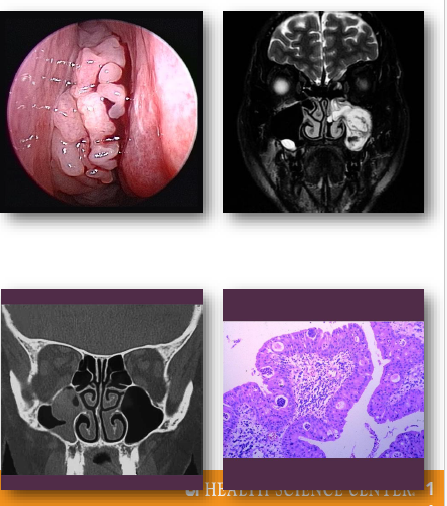

sinonasal papillomas overview

Benign epithelial tumors of sinonasal mucosa

•Includes inverted and exophytic variants

•Associated with HPV infection in some cases

•Locally aggressive with recurrence potential

•Small risk of malignant transformation exists

sinonasal papillomas clinical features

•Unilateral nasal obstruction or visible mass

•May present with epistaxis or discharge

•Often arises from lateral nasal wall

•May extend into adjacent sinus spaces

•Symptoms depend on size and location

sinonasal papillomas management and prognosis

•Surgical excision required for treatment

Complete removal reduces recurrence risk

•Long-term follow-up recommended

•Recurrence relatively common

•Small risk of malignant transformation

fungiform sinonasal papilloma

inverted sinonasal papilloma